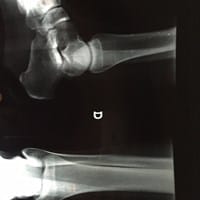

Segunda opinion rx tobillo derecho

Fui al traumatólogo y me dijo que podría tener osteocondritis, me mandó resonancia y radiografía, la resonancia la recojo el miercoles, que tal ve la radiografía, ¿Podria ser? Le adjunto la radiografía antes se me olvidó: